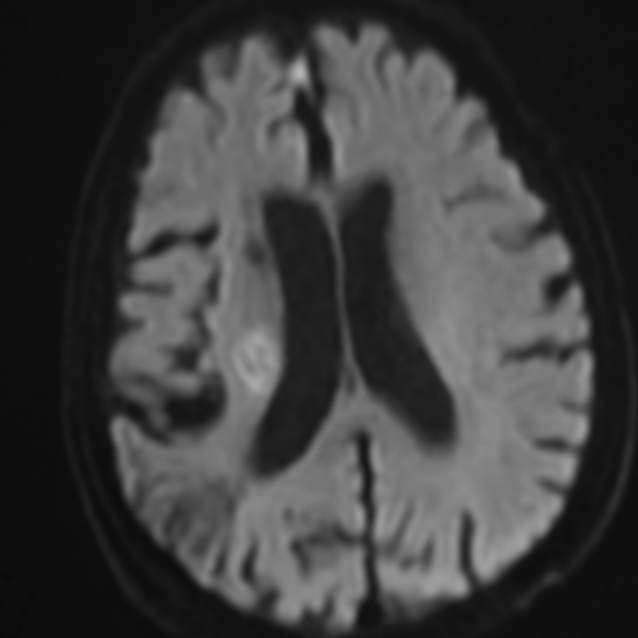

老人家进入医院全面评估后,发现右侧颅内一个主血管存在多节段局限性卡脖子的狭窄,TTP较对侧明显延长,呈缺血状态………,医院多学科讨论评估后,给予第一次外科干预后,患者瘫痪的肢体活动有改善,家人很开心……;在第二次干预之前,又出现了小的新发脑梗塞,继续药物保守治疗,可能还会梗塞;外科干预吧,刚刚出现新发的梗塞,出血风险大,况且又是高龄老年人,血管条件都是个未知数………。本来计划好的二期干预方案受到挑战,面对两难尴尬境地,所有的家人都一时难以决定:向左走?向右走?还是原地踏步进行观望?